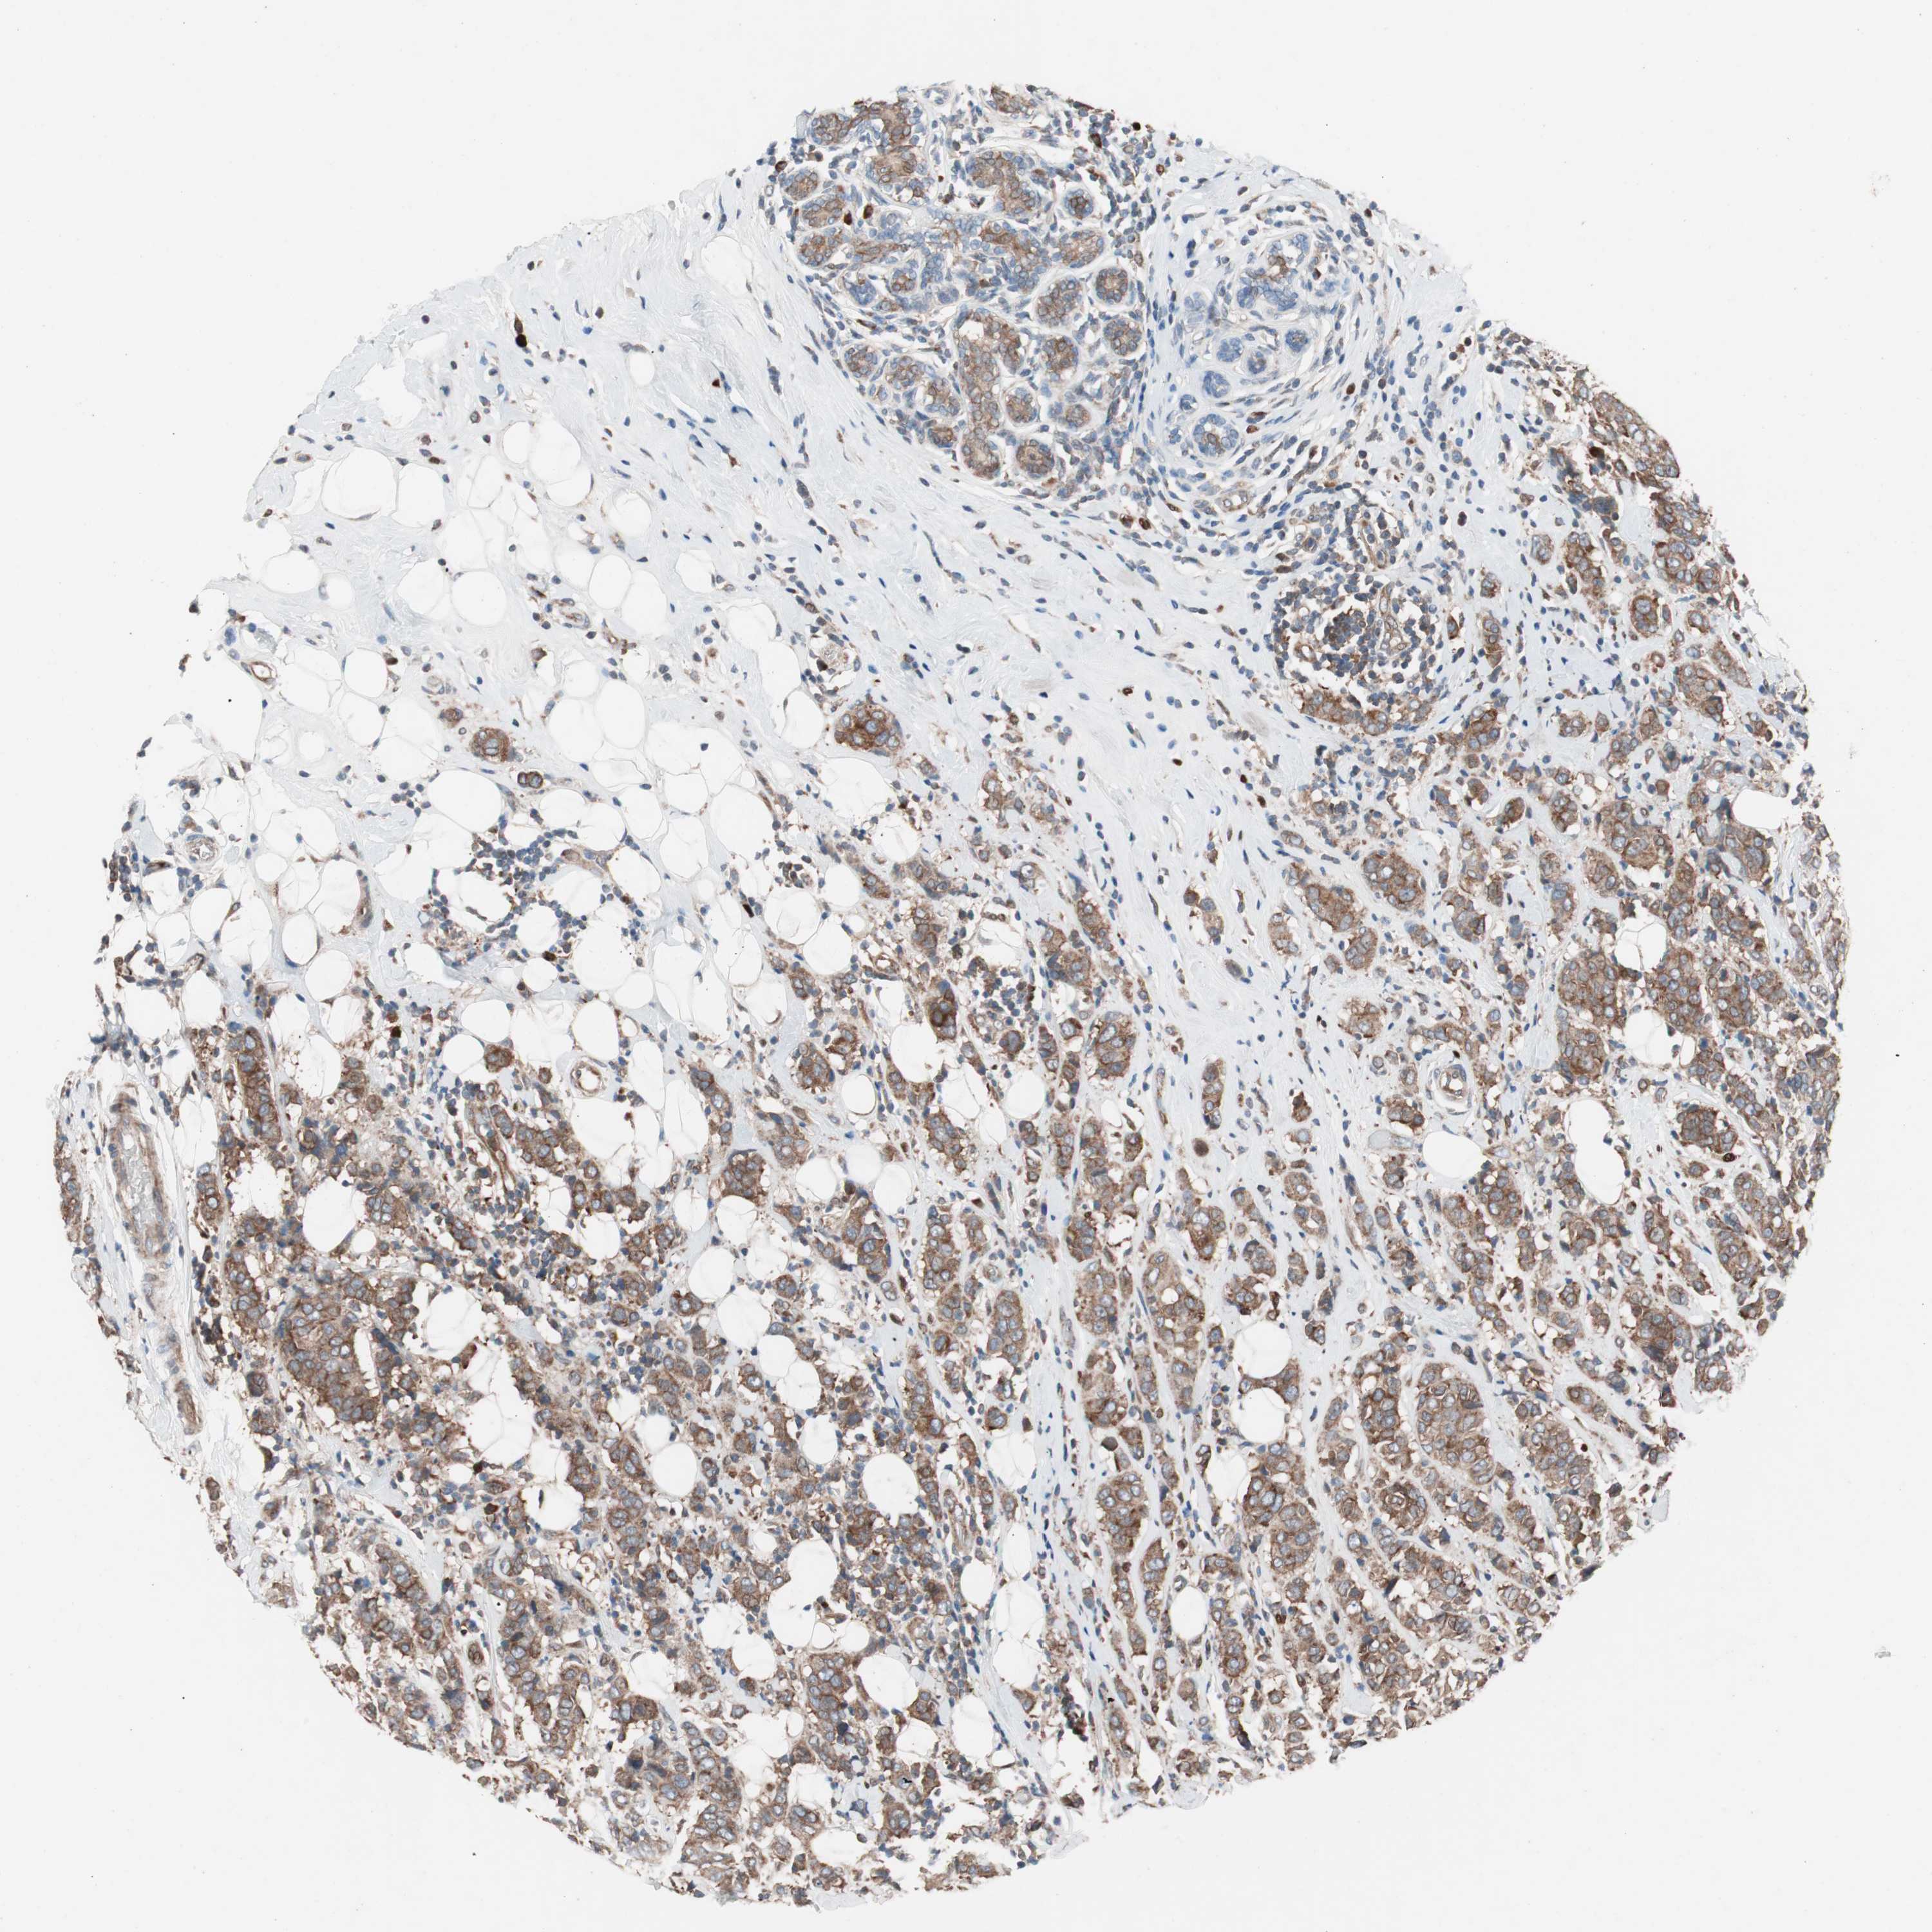

CANCER BREAST CANCER Show tissue menu

BRCA TCGA BRCA VALIDATION PROTEIN EXPRESSION